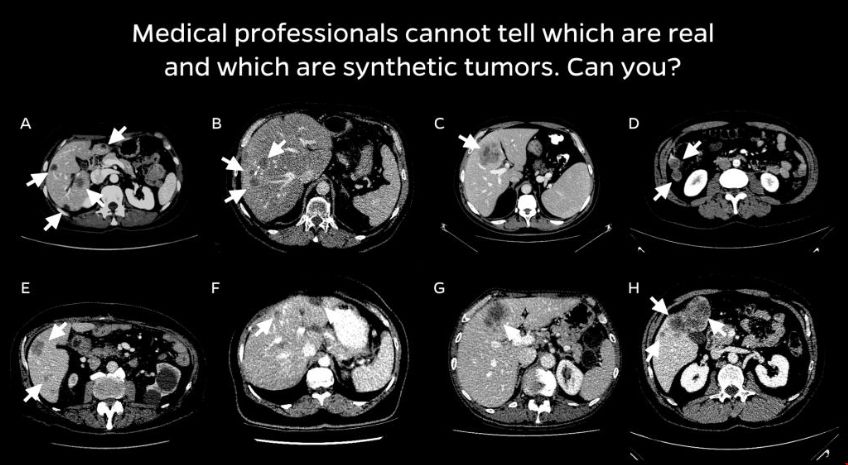

該團隊與放射科醫生合作,設計了一種四步合成現實腫瘤的方法。首先,他們為人造腫瘤選擇了避免與周圍血管碰撞的位置。接下來,他們添加了隨機的“噪聲”模式,這樣他們就可以生成在真實腫瘤上發現的不規則紋理,并生成反映真實腫瘤不同輪廓的形狀。最后,他們模擬了腫瘤擠壓周圍環境的傾向,這改變了它們的外觀。研究人員說,合成的腫瘤是超現實的,并且通過了視覺圖靈測試——也就是說,即使是醫學專業人員在視覺檢查中也會把它們和真實的腫瘤混淆。